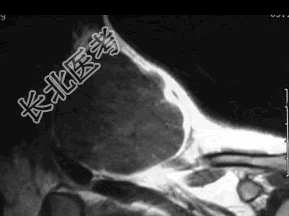

- 多项选择题37岁女性,左侧颈部肿块渐进性增大, 无压痛,局部皮温不高, CT、MRI扫描如图所示,请选择正确的描述或诊断 ( )

A、CT发现左侧颈后三角区可见低密度肿块影

B、增强扫描未见强化

C、MRI的T

WI呈低信号D、MRI的T

WI呈高信号,其内可见分隔E、考虑为淋巴管囊肿